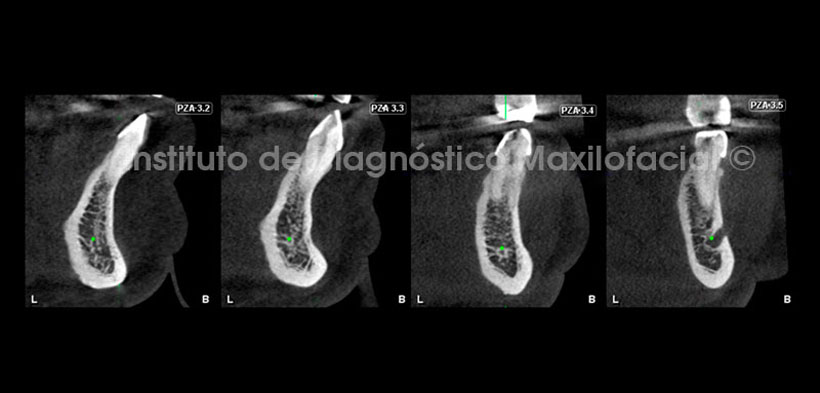

Se realizaron los cortes transaxiales (Fig. 3 y 4) para mostrar la relación del conducto incisivo mandibular con los dientes anteriores, delimitado de color verde la cortical superior de este, y así mismo se muestran el inico de este a nivel del agujero mentoniano. Obsérvese la bifurcación radicular de las piezas 3.4 y 4.4, además del proceso osteolítio a nivel apical en la pieza 4.5.